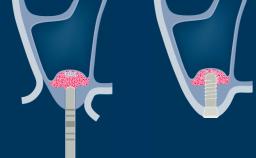

- explain the rationale for contour augmentation using guided bone regeneration (GBR)

- describe the treatment concept and surgical steps for simultaneous contour augmentation